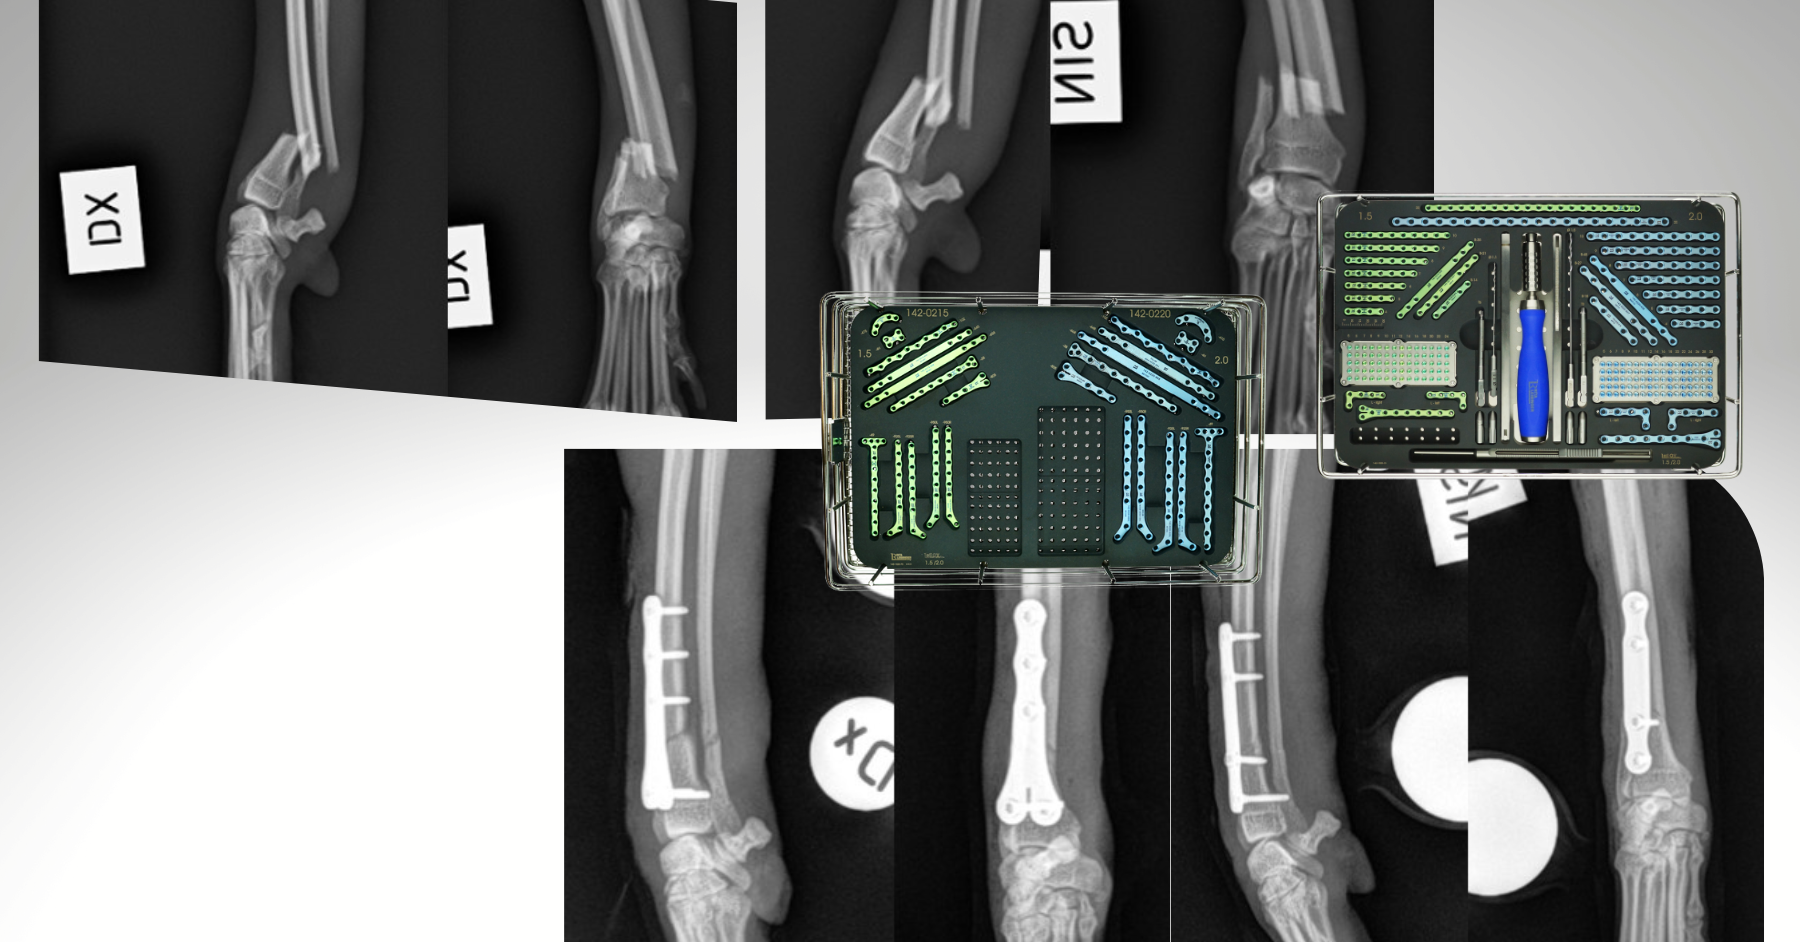

Case Overview In November 2025, Skeeter, a 14-week-old Doodle puppy weighing ...

Products

Pioneering Small PatientOrthopedics with the 1.5 mmLeiLOX TPLO Swing Titanium Plate ...